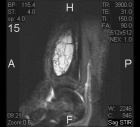

T.K. - 18 year old male with asymptomatic left ankle swelling for several months

Zoom image: Radiological image Radiological image.